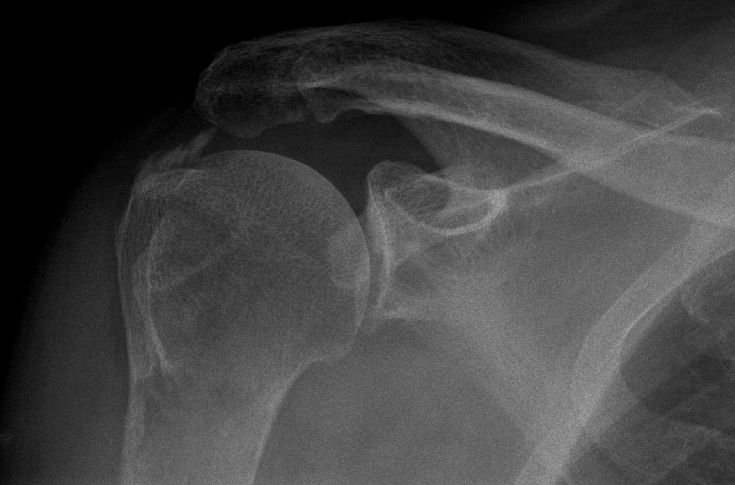

Humerus |

![]() |

![]() | ||||||||||||||||||